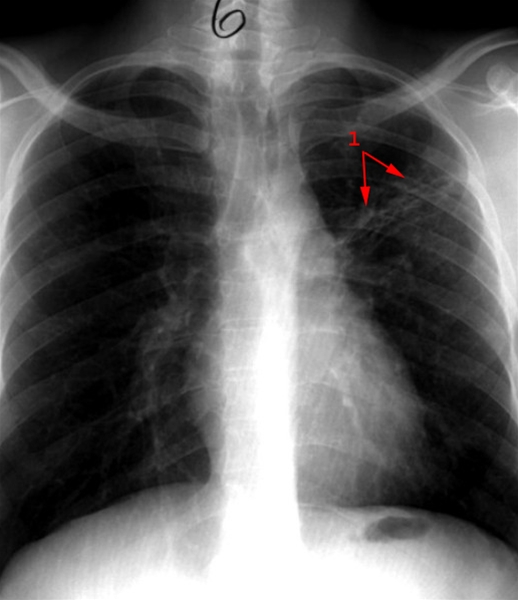

Primær tuberkulose - billede 2

Tilbagegang af forandringer (1) efter behandling med medikamenter.

Se billede 1: primær tuberkulose før behandling, røntgen